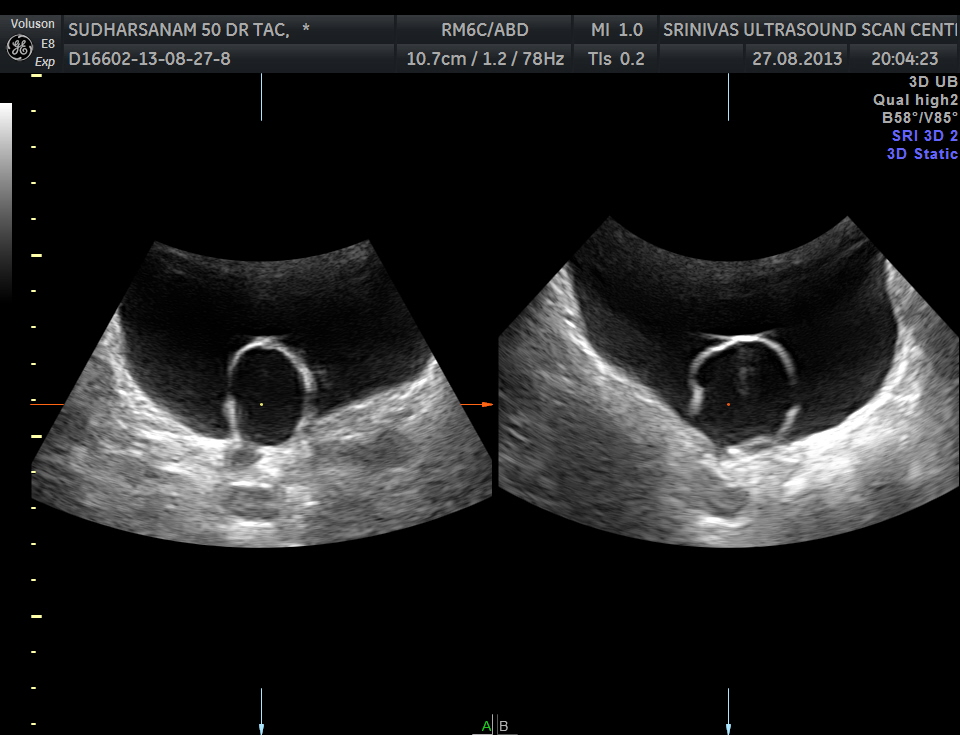

The urinary bladder showed the following :

given below are few other reconstructions